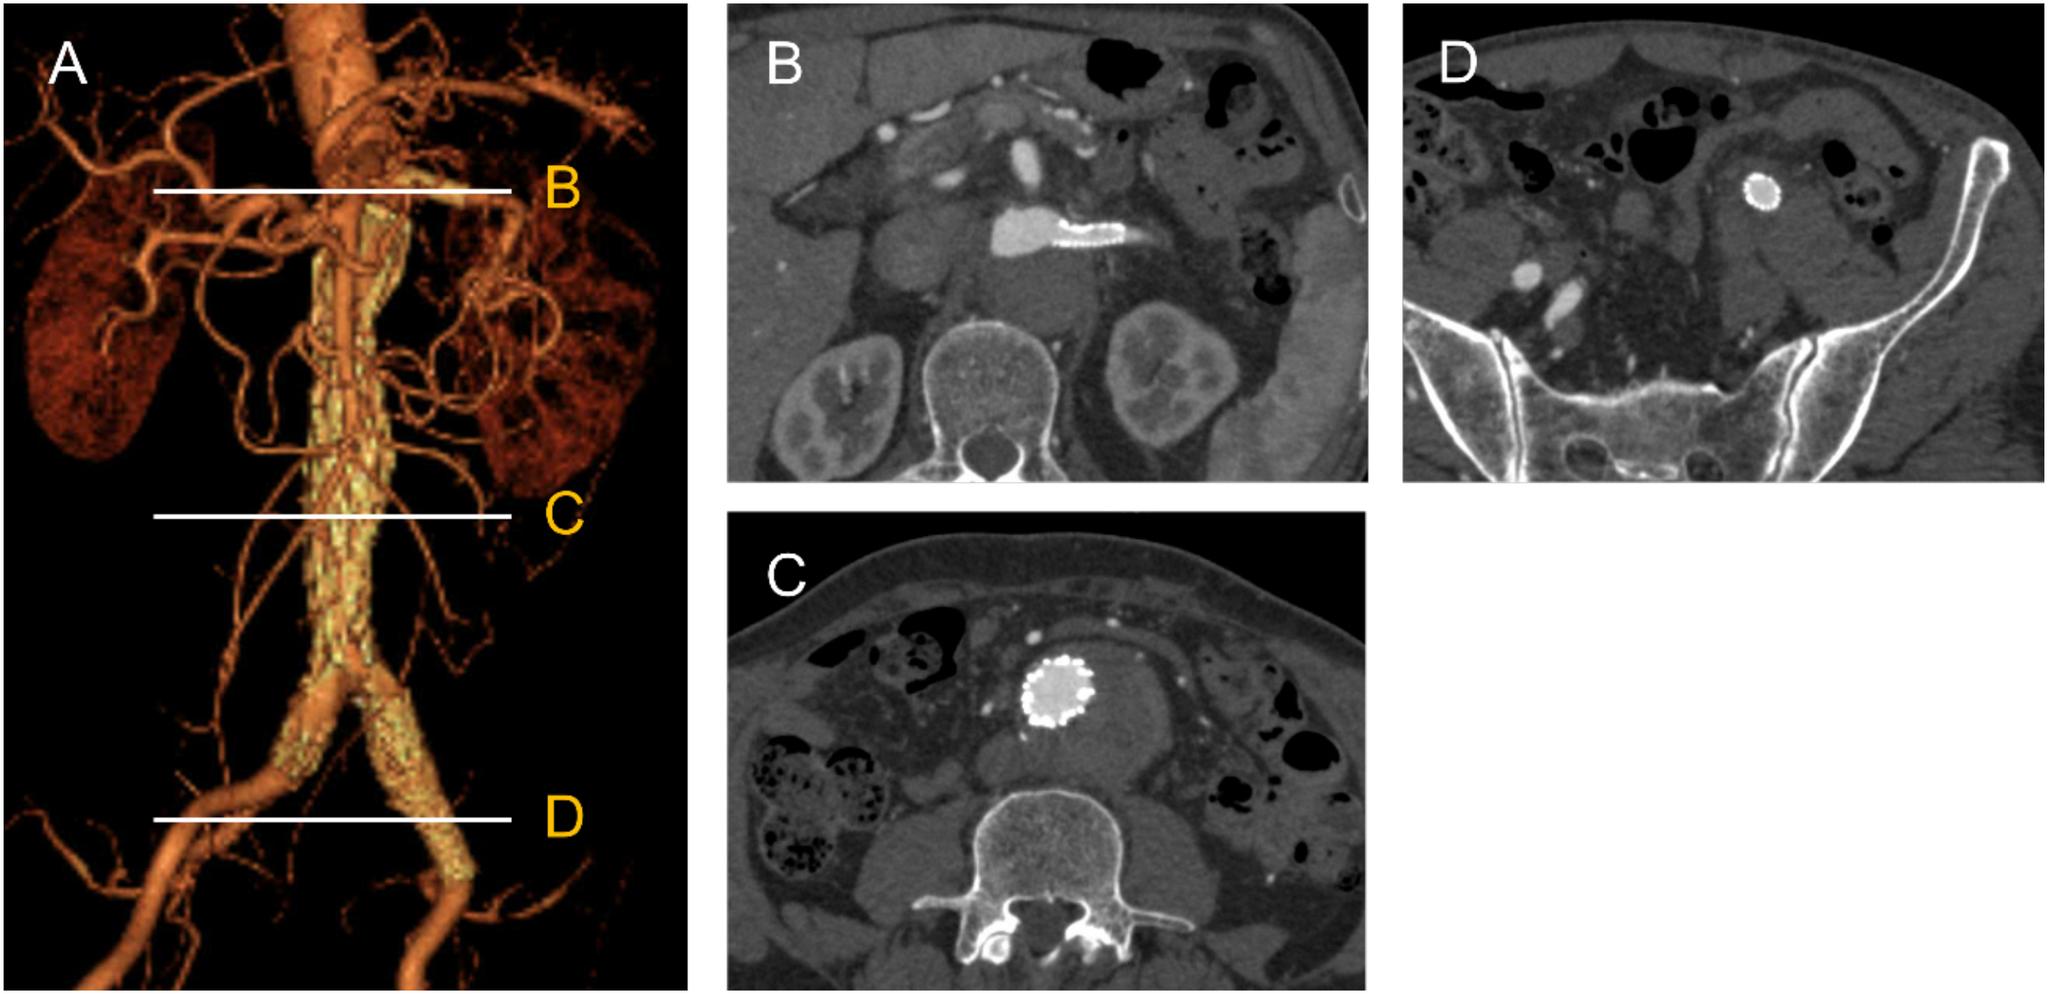

A 66-year-old man presented with an enlarging abdominal aorta false lumen, after type A aortic dissection repair. Residual entries were located at the left renal artery, abdominal aorta, and left external iliac artery. The patient underwent endovascular aortic repair with left renal artery stenting to close the entries. Completion aortography showed no false lumen flow without an endoleak, and contrast-enhanced computed tomography 1 month after the procedure demonstrated complete false lumen thrombosis. A total endovascular approach is possible for abdominal aneurysmal dilation in chronic aortic dissection when all entries can be closed using a one-stage procedure with stent grafts and/or branch stenting.

一名66岁男性在A型主动脉夹层修复术后出现腹主动脉假腔扩大。残余破口位于左肾动脉、腹主动脉和左髂外动脉。患者接受了血管腔内主动脉修复术并置入左肾动脉支架以封闭破口。术后主动脉造影显示无内漏且假腔内无血流,术后1个月的增强计算机断层扫描显示假腔完全血栓形成。当使用覆膜支架和/或分支支架通过一期手术能够封闭所有破口时,对于慢性主动脉夹层的腹主动脉瘤样扩张采用全血管腔内治疗方法是可行的。